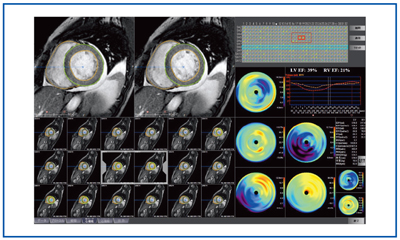

心臓疾患のCTとMRI 第2版 | 佐久間肇, 陣崎雅弘, 北川覚也, 石田, ziostation2を用いて心臓MRI検査の総合的な画像解析を可能に

ziostation2を用いて心臓MRI検査の総合的な画像解析を可能にEVTテクニック これは困ったどうしよう/南都伸介(著者),飯田修(著者)